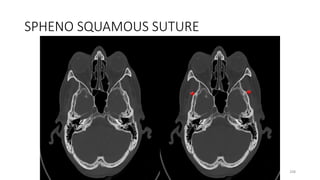

Sphenosquamous suture

SPHENO SQUAMOUS SUTURE